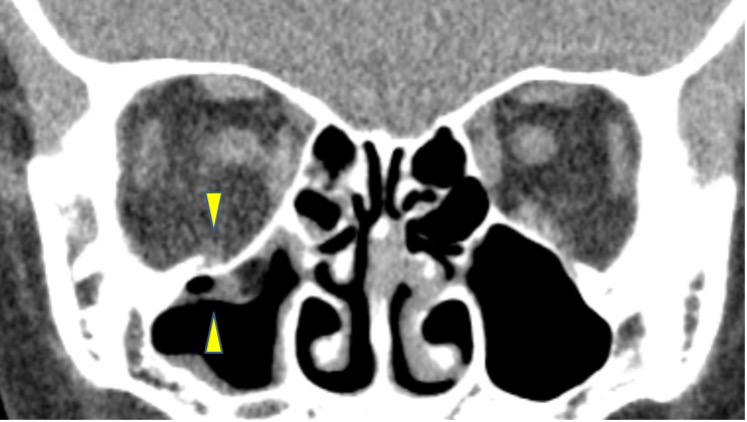

眼窩内壁が偏位し、篩骨洞内に突出している。内直筋が内側に偏位し、腫大しているように見える。(矢頭)

眼窩下神経管周囲がヒンジとなっている。(矢頭)

折れた骨は上顎洞内に偏位している。

眼窩内壁の骨折があり、篩骨洞がつぶれている。(矢頭)

眼窩脂肪が偏位・嵌頓し、それに伴って視神経の弯曲も見られる。